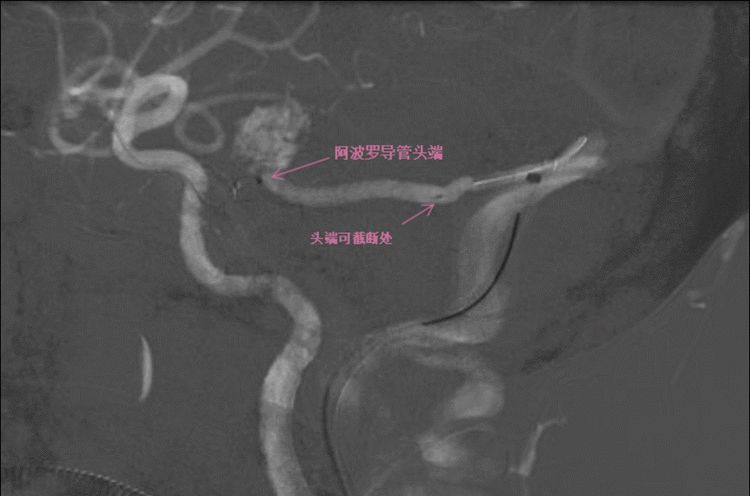

将navien导引导管经股静脉导管鞘超选到右侧乙状窦。用Traxcess14导丝将阿波罗导管经navien超选到回流静脉畸形团处。

静脉端持续打胶。